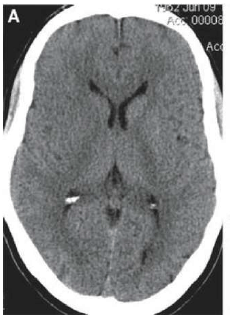

Paciente do sexo masculino, 60 anos, admitido em departamento de emergência com quadro insidioso e progressivo de redução de força e sensibilidade no hemicorpo esquerdo há mais ou menos 2,5 horas. Tem antecedente de hipertensão arterial e dislipidemia há mais de 20 anos, em tratamento irregular com losartam, hidroclorotiazida e atorvastatina. Ex-tabagista. Ao exame físico, paciente com abertura ocular a estímulos verbais, contactuante e obedecendo comandos simples. Apresenta hemiparesia e hipoestesia em hemicorpo esquerdo. Ritmo cardíaco regular, frequência cardíaca 90bpm, pressão arterial em membros superiores e inferiores (deitado) 190x100mmHg, frequência respiratória 19ipm, SpO2 88%. Tomografia de crânio evidenciou o resultado a seguir.